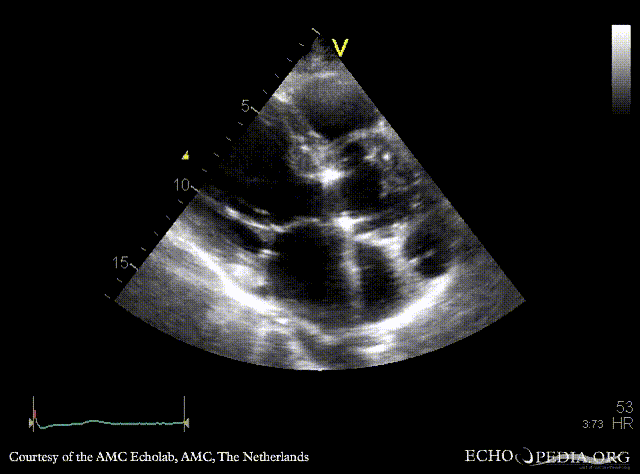

Case 37

Abscess of aortic root

PLAX: dilated aortic root, abscess of aortic root PLAX: dimensions of the abscess